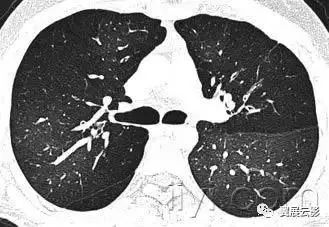

十八、小叶中心性:

小叶中心性异常包括(1)结节(2)树芽征,提示小气道病变(3)由于临近间质的增厚或者浸润导致小叶中心结果更加清晰(4)小叶中心性肺气肿导致的异常低密度。

附图为小叶中心性肺气肿